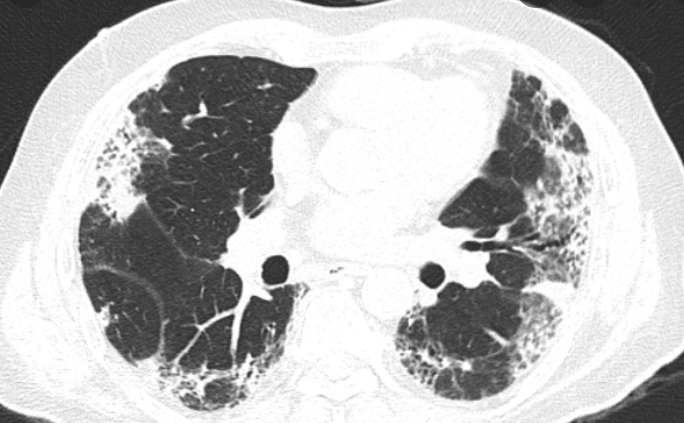

Hình ảnh Xơ phổi ở bệnh nhân Hậu Covid